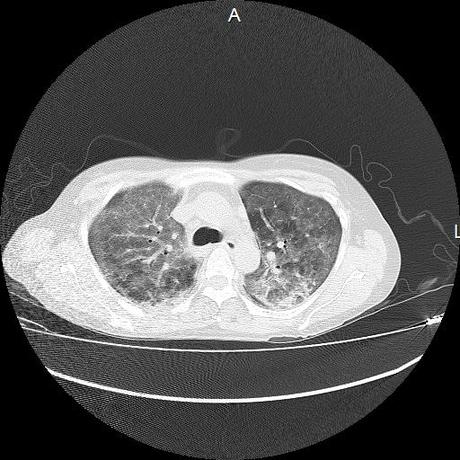

El parénquima pulmonar con areas parcheadas difusas en vidrio despulido combinadas con otras areas hipodensas de baja atenuación debidas a atrapamiento aéreo y engrosamiento intersticial y zonas de fibrosis de predominio en lóbulos medios e inferiores de ambos pulmones.

- LOS HALLAZGOS PUEDEN ESTAR EN RELACIÓN A NEUMOPATIA INTERSTICIAL PROBABLE ETIOLOGIA HIPERSENSITIVA VS AUTOINMUNE/BACTERIANA/FUNGICA.